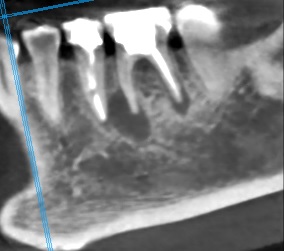

Здравствуйте! Стоит ли вкладываться в эту восьмерку ?Если да, то насколько срочно? Сложная в гигиене, но в остальном никаких претензий к зубу нет. Уже один раз пломбировал. Сегодня случайно обнаружил, что там опять кариес, причем довольно приличный. Удивляюсь, как раньше не заметил.

Нажмите на изображение для увеличения

Название: viber_image_2019-06-04_23-14-36.jpg

Просмотров: 40

Размер:	24.8 Кб

ID:	13136068

Цитата Сообщение от Gothicman Посмотреть сообщение

Вложение 13136068

...если учитывать только обозримый участок (хронический процесс), то срочности большой нет, 1-2 мес. погоды не сделает. Снимок бы дал более полный прогноз. Лечить можно и нужно.